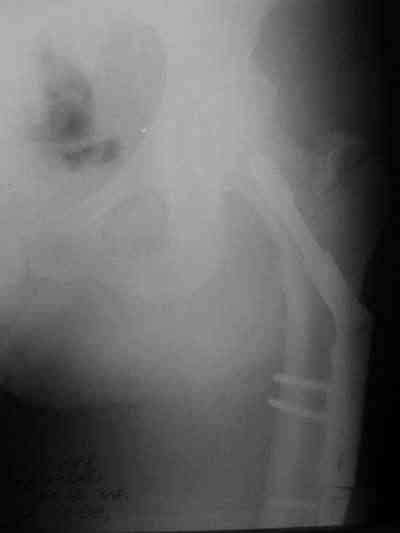

Снимки в приложении.

Конечно, при современном подходе, применение PFNa удленной версии со спиральным лезвием было бы адекватным решением. А также еще далеко до малоинвазивной техники, представленной А.Ю.Семенистым в издании Margo Anterior (МАТИС и AO/ASIF), где выполняется имплантация DHS через 4 сантиметровый разрез, снимаю шляпу перед этими мастерами, просто - высший класс, но ... какие наши годы!! ;-)

В приложении и имеющийся в наличии брейс. Приношу извинения за низкое качество снимков.